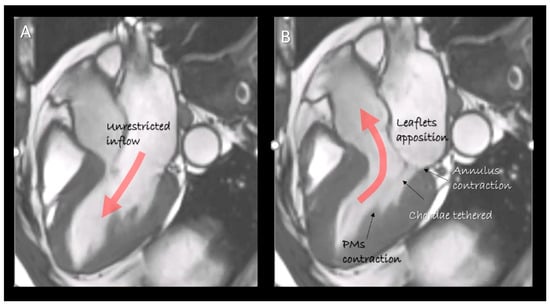

Figure 1.

Cardiac magnetic resonance (CMR) still frame image in cross-section long-axis view in (A) diastole and (B) systole showing the mitral valve apparatus formed by leaflets, annulus, chordae tendinea and papillary muscles. They move in a perfect spatial and temporal coordination to obtain an effective competence and an unrestricted inflow. The “dynamic” anatomy provided by non-invasive imaging techniques gives us the awareness as the structural arrangement of any single component serves to a specific function.

This review describes the anatomy of the components of the MV apparatus, as revealed by the aforementioned non-invasive imaging techniques, highlighting physiological, pathological, surgical and interventional implications related to specific anatomical structures (Figure 1).